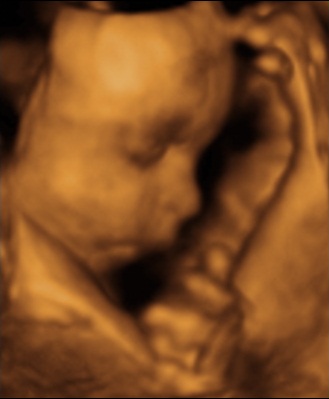

We went through the usual process of the 12-week and 20-week scans, but these are far from exact. I had to know if we were having a carrier daughter or an MD-free son.

I suggested we go for a 4D scan, confused about the 4th dimension as I understood that to be time. Once I knew, I could process the reality and then focus on my best damn dad ambition.

Thanks to Groupon, we got a neat little deal and booked ourselves in for a scan. As the imaging scan took place, we were treated to a short film of our unborn child displayed on a large screen.

And there it was in black and white (and sepia): we were having a girl, and my child would be a carrier.